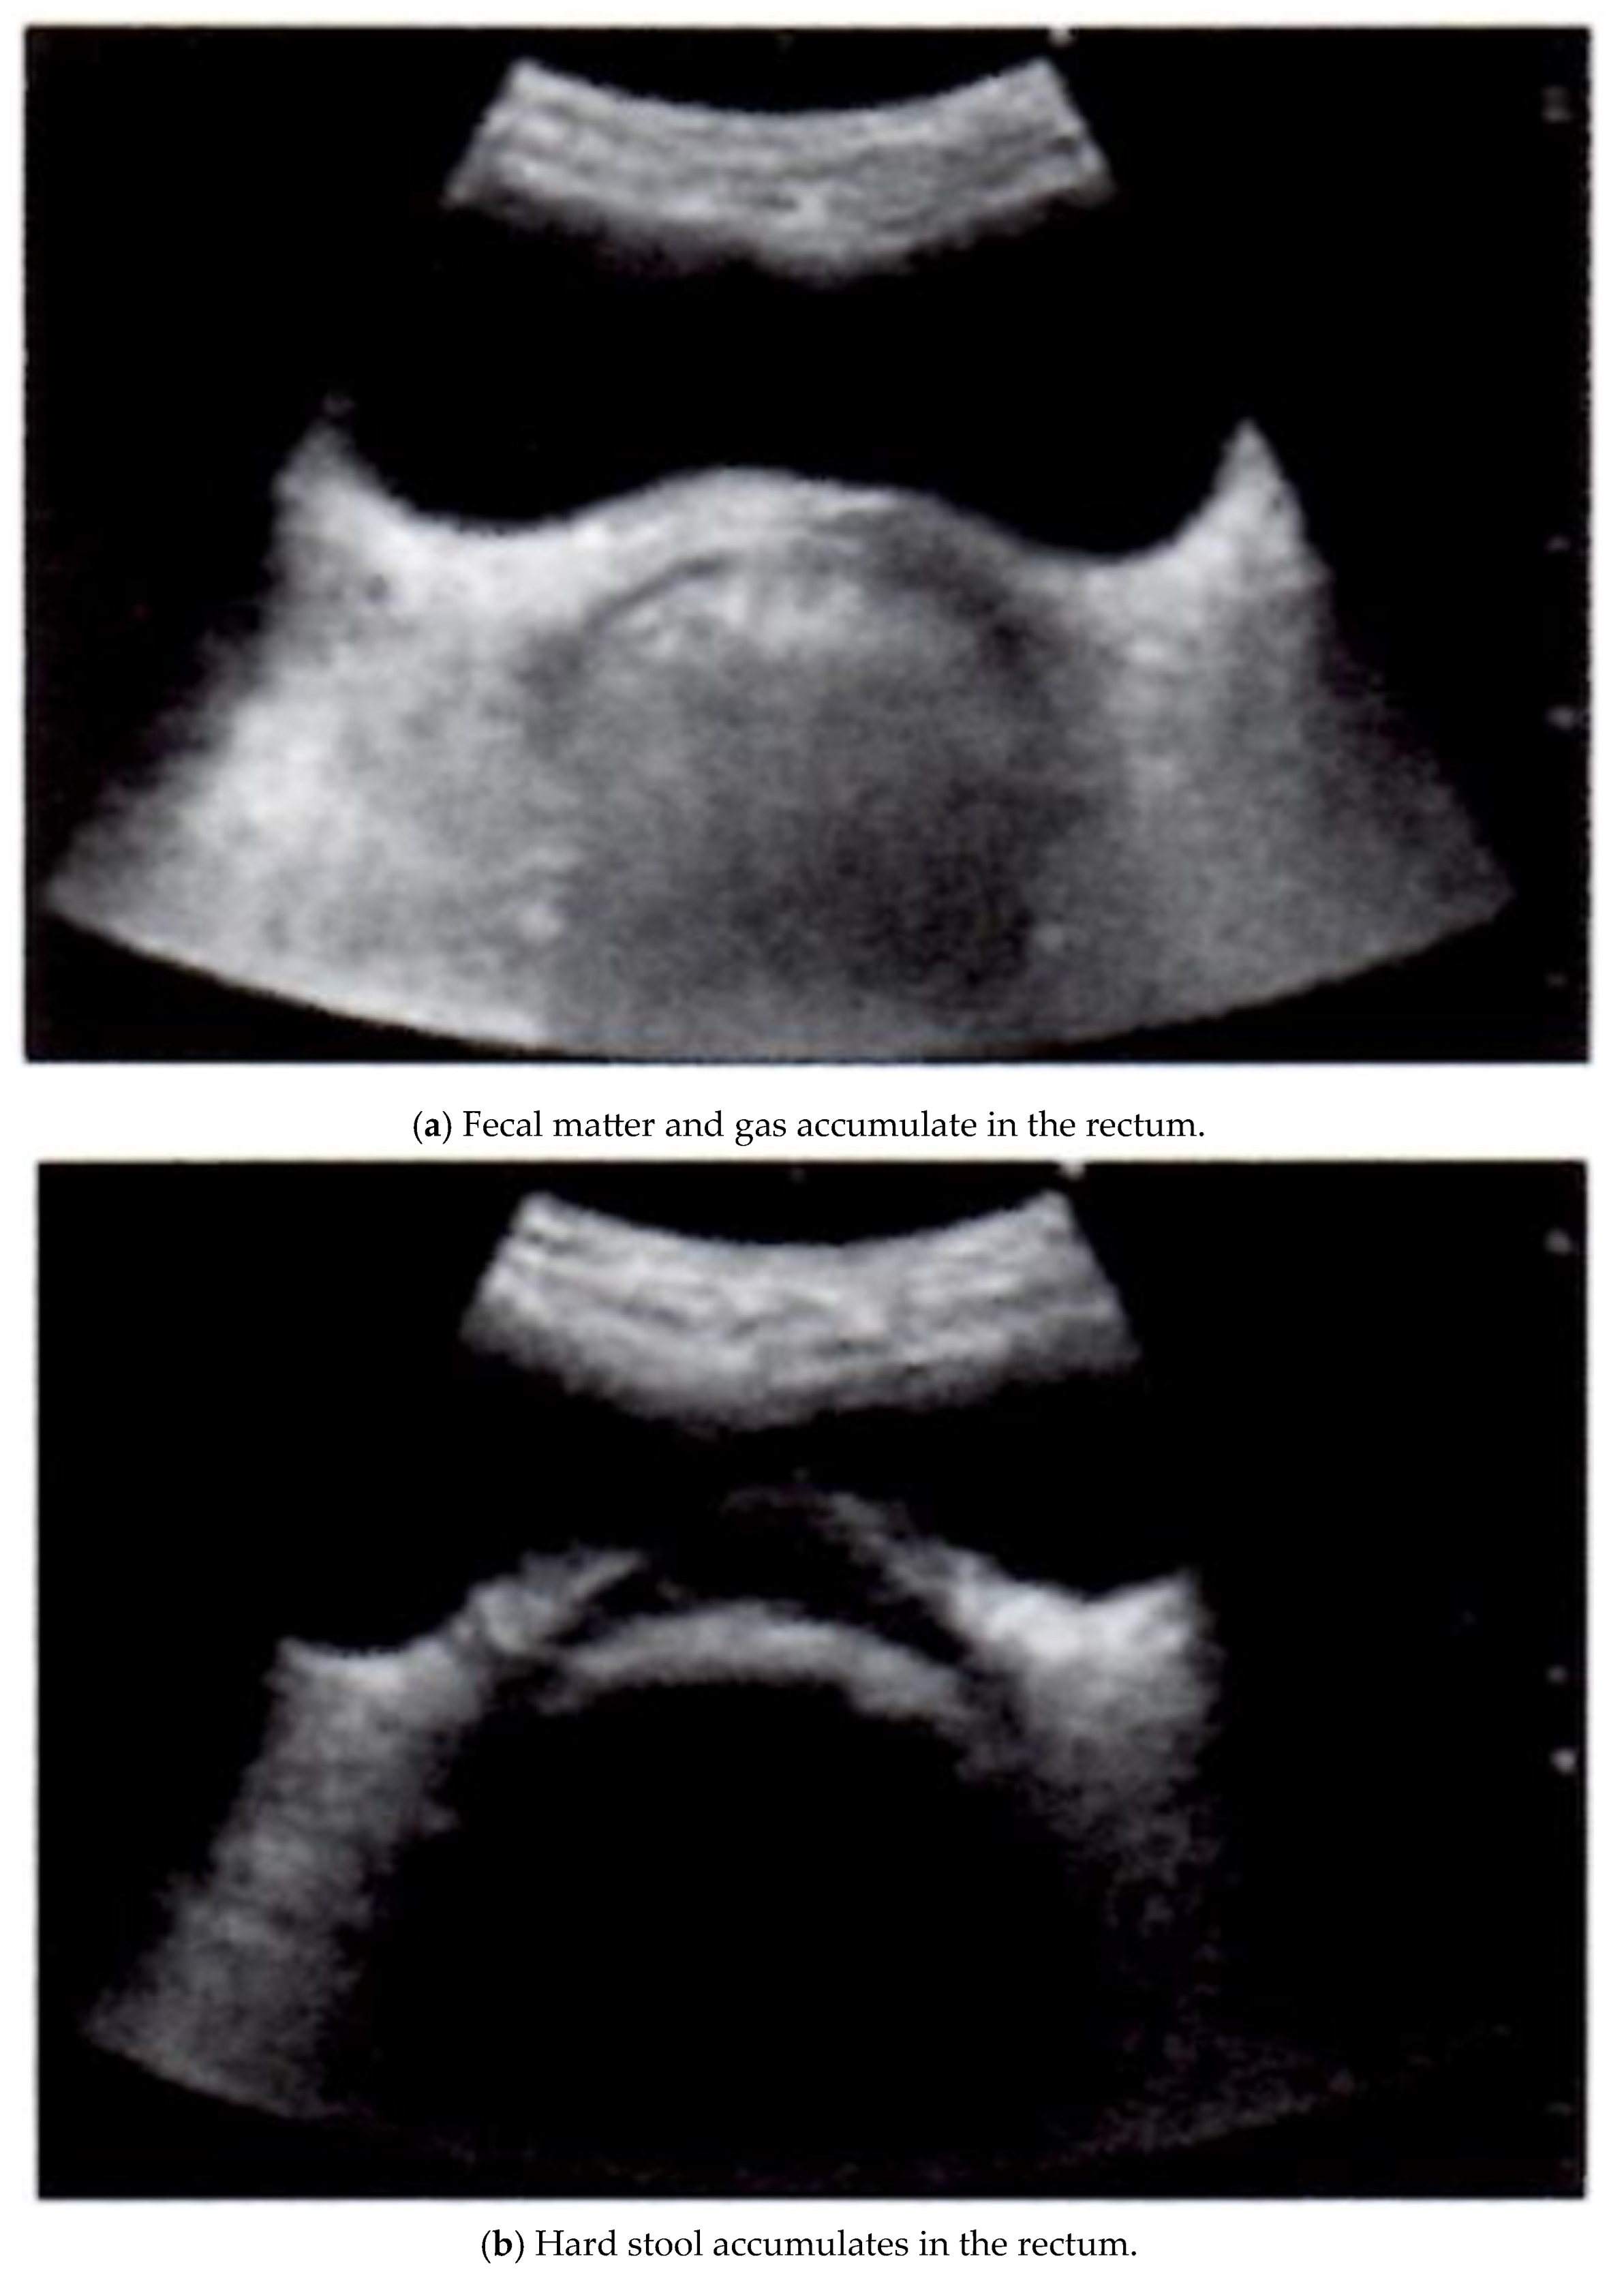

However, owing to recent improvements in device performance, the clinical application of noninvasive, low-cost, simple, and repeatable ultrasound imaging equipment for gastrointestinal diseases has attracted increased attention. Ultrasound-based methods have attracted particular attention because of their many inherent advantages, such as wide availability, bedside availability, and relatively low cost. Several ultrasound techniques have been developed using different excitation methods (Table 1) [24,32]. Several reports have described the clinical application of ultrasound imaging equipment for the treatment of chronic constipation [33,34,35,36]. In recent years, a research group consisting of multidisciplinary staff involved in chronic constipation treatment has proposed a simple functional evaluation method for chronic constipation treatment using rectal echocardiography [36]. This evaluation method classifies the state of fecal retention in the rectum into three patterns (Figure 1a–c). This image is quoted from Reference 36 with some modifications. The presence or absence of rectal fecal retention and the quality of the stool can be evaluated by recording a cross-sectional image of the rectum via ultrasound. In cases of fecal accumulation in the rectal lumen, echoes were reflected from the surface of the content located deeper than the bladder, and a half-moon-shaped hyperechoic area was visualized on a cross-sectional image (Figure 1a). In addition, when hard stool accumulates, acoustic shadows occur (most of the ultrasound waves are reflected by strong reflectors), and the ultrasound waves do not reach the distal side of the body. As a result, there is no sound behind the reflector. A crescent-shaped hyperechoic area is visualized, in which echo or hypoechoic activity is observed (Figure 1b) [37]. If the rectum was free of stool or gas, no obvious hyperechoic area was visualized. On cross-echo images, a circumferential hypoechoic area was observed as an empty intestinal tract (Figure 1c).

Figure 1.

Evaluation of fecal retention in the rectum using ultrasound imaging equipment (this image is from [36] with some modifications): (a) fecal matter and gas accumulate in the rectum. The presence or absence of rectal fecal retention and the quality of the stool can be evaluated by recording a cross-sectional image of the rectum via ultrasound. In cases of fecal accumulation in the rectal lumen, echoes are reflected from the surface of the content located deeper than the bladder, and a half-moon-shaped hyperechoic area is visualized on a cross-sectional image. (b) Hard stool accumulates in the rectum. When hard stool accumulates, acoustic shadows (most of the ultrasound waves are reflected by strong reflectors) do not reach the distal side of the body. As a result, there is no sound behind the reflector. A crescent-shaped hyperechoic area is visualized in which echo or hypoechoic activity is observed. (c) There is no retention of feces in the rectum. When the rectum was free of stool or gas, no obvious hyperechoic area was visualized. On cross-echo images, a circumferential hypoechoic area may be observed as an empty intestinal tract.

In the future, this classification system is expected to be useful in clinical applications to determine treatment strategies [36]. In other words, if the rectum is free of feces, as determined by ultrasound imaging, there is no need to administer an enema; if hard stools are found, dissection can be performed to prevent complications such as severe intestinal perforation due to subsequent administration of laxatives. In addition, if normal stool is confirmed in the rectum using an ultrasound imaging device, treatment for constipation by encouraging defecation with suppositories, which has been based on trial and error, will hopefully become more consistent with the disease state [36].